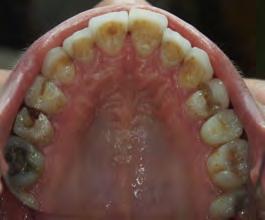

Two authors had access to the data and all information was de-identified. Study personnel made no contact with patients at any time throughout the study, and no PHI was recorded. Re corded data included diagnosis (clinical and/or pathologic), basic demographics (age, gender), and current prescription medica tions. For cases that were not biopsy-proven, the standard clinic protocol is that the clinical presentation must exhibit the charac teristic white Wickham striae for a patient to be given the clinical diagnosis of OLL or OLP (Figure 1). Any clinical diagnosis of OLL or OLP was rendered by one of four oral medicine experts in the Oral Medicine Clinic, and biopsy was performed in cases with any doubt.

Figure 1. Example of characteristic Wickham striae and reticular pattern on buccal mucosa used to clinically diagnose OLL and OLP cases. Erythematous areas also seen. Figure 2. Frequency and percent of study patients using specific medications with color-coded drug classes.